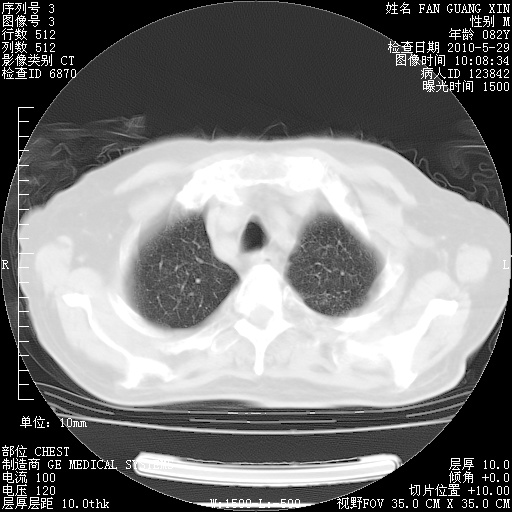

再治疗10天后的肺部CT

再治疗10天后的肺部CT 纵膈窗

阅读此次胸部CT,肺间质渗出性改变较入院时有吸收。目前从体温、白细胞、中性分叶明显增高,肯定存在细菌感染(发生医院感染哦,若无消化道及泌尿系统等感染的依据,肺部感染可能大)。若你院头孢哌酮舒巴坦钠耐药率较高,同意你的方案,若48小时体温仍高,可考虑使用碳青霉稀类抗菌药物,同时可予超声雾化、注意滴数时加大液体量。白蛋白33.30g/L较低哦,需加强营养等支持治疗。